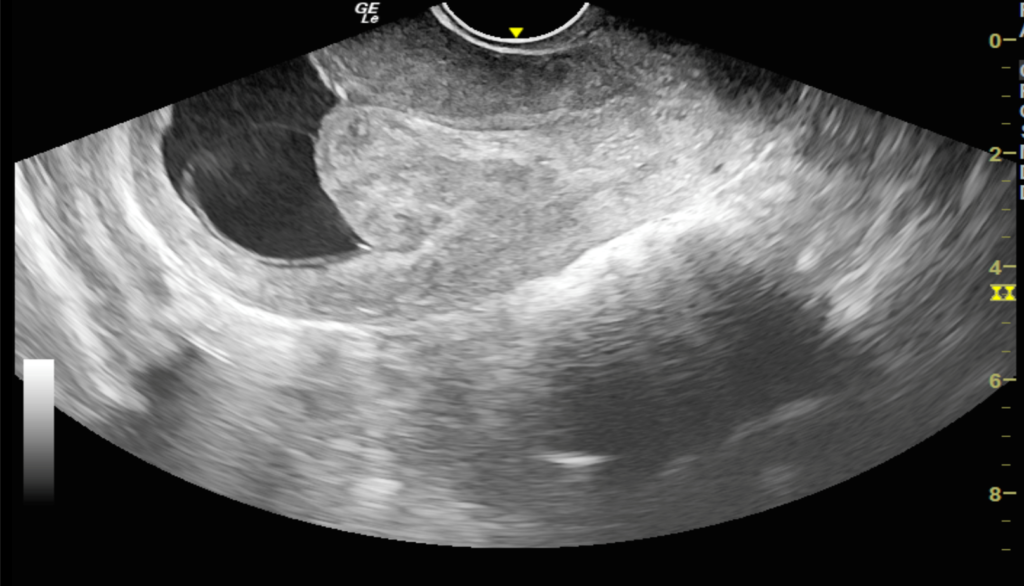

We report a case of a 24-year-old lady who was unable to conceive for a period of 8 years. Infertility workup was negative. In 2018, she conceived, however cardiac activity was not demonstrated in the fetus and eventually medical abortion was performed. Transvaginal sonography was performed for the same at a private center which did not pick up any uterine structural abnormality. In 2021, the patient presented to our emergency department with a 14-week gestation pregnancy with complaints of bleeding per vaginum for 2 days. Antenatal transvaginal ultrasound was performed for confirmation and viability of an intrauterine pregnancy. An intrauterine gestational sac with crown rump length corresponding to 8 weeks 5 days and absent cardiac activity was seen suggesting the diagnosis of missed abortion (Figure 1). Surrounding the gestational sac was fluid with internal echoes suggesting failure of implantation (Figure 2). A well-defined uniformly echogenic pedunculated lesion was seen in the endometrial cavity (Figure 3). As it was traced towards the point of its origin, a focally hypoechoic region was demonstrated interrupting the hyperechoic endometrial lining (Figure 4), classically described as the ‘interrupted mucosa sign’ [2]. On colour doppler image, a single vascular pedicle was demonstrated (Figure 5), known as the ‘pedicle artery sign’ [3]. Based on these classical features the diagnosis of an endometrial polyp was made. It was seen to abut the gestational sac suggesting mechanical hindrance to growth of the embryo (Figure 6). On real time imaging, the endometrial polyp was seen prolapsing from towards the uterine fundus to the lower uterine segment (Figure 7). For better characterization of the endometrial polyp, it has been recommended to distend the uterine cavity with saline (also known as saline infusion sonohysterography) [4,5], however in our case it was unwarranted because the gestational sac and fluid naturally distended the uterine cavity and helped in optimum visualization (Figure 4,6). Figure 8 depicts another case of an endometrial polyp showing a non-gravid uterus with an echogenic lesion in the endometrial cavity showing the classical interrupted mucosa sign (Figure 8A) and the feeding artery sign (Figure 8B).

Figure 2. Transvaginal sonography shows a gestational sac within the endometrial cavity without a definite site of implantation. Note the surrounding echogenic fluid.